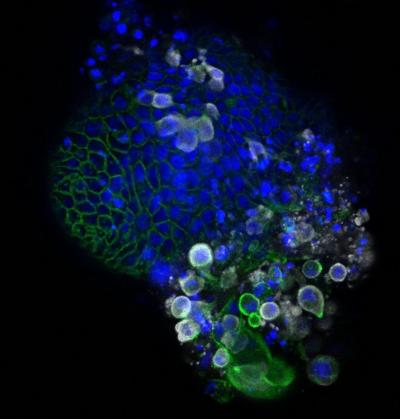

स्कॉटलँड स्कूल ऑफ लाईफ सायन्सनी कोरोना व्हायरसच्या काही प्रिंट्स फोटो दाखवले आहेत. त्यात असं दिसून येत आहे कोरोना व्हायरसचं आतड्यांवर फक्त संक्रमण होत नसून कोरोना आतड्यांमध्ये वेगाने पसरत जातो.

माणसाच्या शरीराला संक्रमित करून आतड्यांपर्यंत पोहोचत असलेला कोरोना व्हायरस पांढऱ्या रंगाचा दिसतो. कोरोनाचे निरक्षण करण्यासाठी शास्त्रज्ञांनी अल्ट्रा पॉवरफुल मायक्रोस्कोपचा वापर केला.

शरीरातील कोरोना व्हायरसची माहिती देणारे हे फोटो ३० ते ५० गीगाबाईट्सचे आहेत. स्कूल ऑफ लाईफ सायन्सचे क्वारंटाईन सेल बायोलॉजी प्रोफेसर यांनी सांगितले की, कोरोना व्हायरस आतड्यांपर्यंत पोहोचून शरीराचं नुकसान करत असतो. आतड्यांमध्ये व्हायरसची संख्या वेगाने वाढत जाते.

संशोधकांनी यावेळी माणसांच्या आतड्यांचे परिक्षण करत असताना एका तपासणी ट्यूबमध्ये यशस्वीरित्या व्हायरसच्या नमुन्यांना विकसीत केलं आहे. यानंतर व्हायरसचा परिणाम आतड्यांवर कशा पध्दतीने होत आहे. यावर परिक्षण करण्यात येईल.